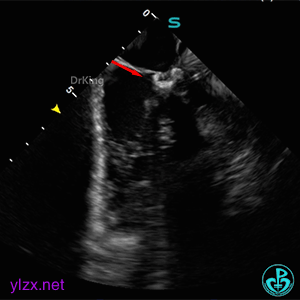

ICE下多切面观察封堵器形态及瓣膜活动状况

封堵器骑跨于室间隔两侧,周围瓣膜正常摆动。

锁定封堵器后观察位置形态

锁定后可见位置形态完好,盘面平整,扣合良好,无周围瓣膜影响。

封堵器完全释放后位置、形态观察

封堵器完全释放后盘面平整,呈“工”字型骑跨于室间隔两侧,未见瓣膜影响。